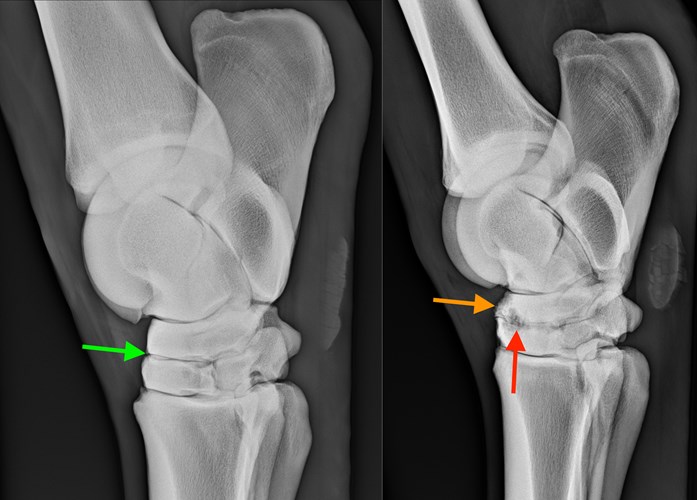

- Arthritis and joint disease

In this lecture Melanie Perrier, Lecturer in Equine Surgery at the RVC, will give an insight into what arthritis is, the causes and the pathology. Discover how to recognise the common clinical signs in horses with degenerative joint disease and what investigatory tools are used to confirm the diagnosis. Learn about the very latest treatment options that can be used to keep horses with arthritis comfortable and how to optimise performance – its more than just bute!